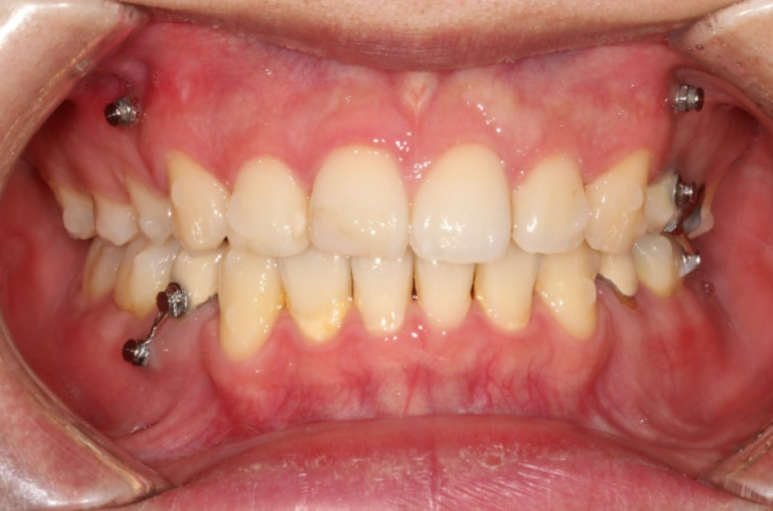

24년 3월까지, 1년 3개월간 70개의 장치를 일주일 간격으로 모두 낀 후 모습입니다.

24.03

중심선은 많이 개선되었으나 여전히 약간의 불일치가 남아있습니다.

1차 세트를 마쳤을 뿐인데도 교합이 좋은편입니다.

앞니 사이 벌어진 틈이 있습니다.

발치공간 1mm가량 남았네요.

이 부분들을 더 개선하고자 재제작에 들어갔습니다.